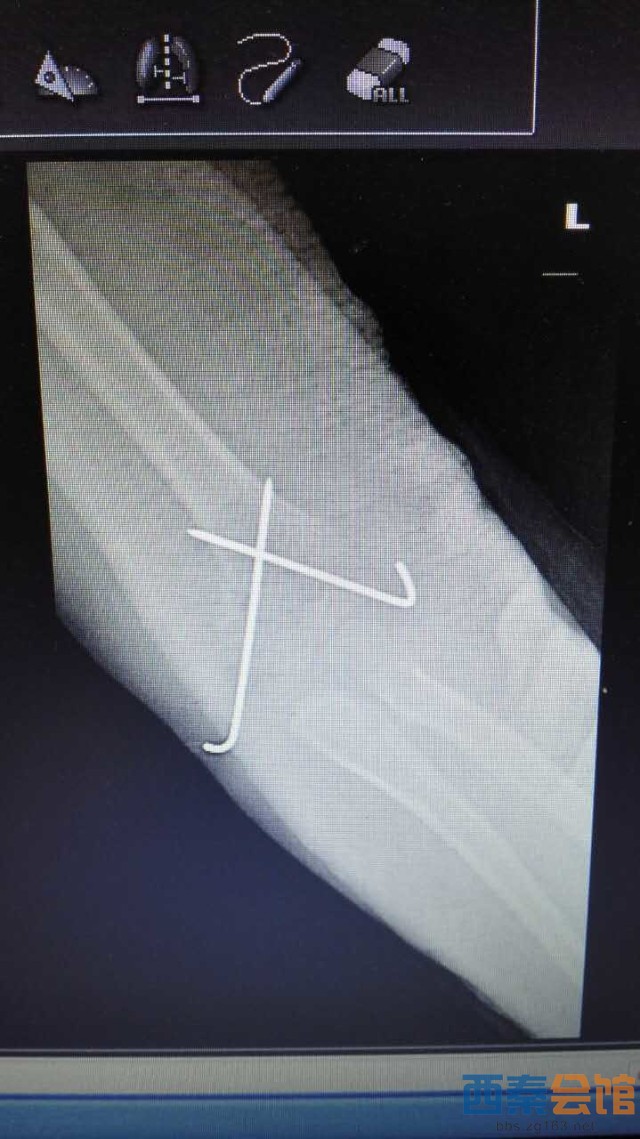

肱骨髁上骨折为儿童常见病,往往需要手术治疗,常规手术为做肘关节内外侧切口,交叉克氏针固定,手术创伤大,伤口瘢痕长,不美观等问题。市三医院骨一科梁涛主任根据患者需求,新引进儿童肱骨髁上骨折前路手术,仅3cm小切口切开复位后,于肱骨内外髁闭合穿针内固定,伤口皮内缝合,不需要拆线,术后伤口愈合快,术后4周可去除石膏托锻炼,术后6周可拔出克氏针,具有创伤小、美观、患者护理方便等优点。目前该5岁患者恢复良好,已出院休养。